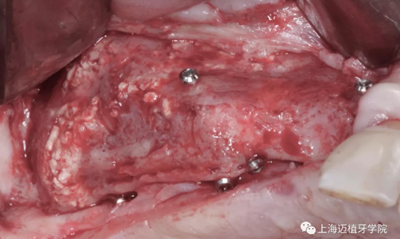

利用BBA植骨法,骨片固定頰舌側(cè)距離

中間填充自體骨屑

用骨釘固定骨板

四個(gè)月后成骨

植入植體

成骨的效果非常好,植入時(shí)可以見血液外滲,血運(yùn)良好